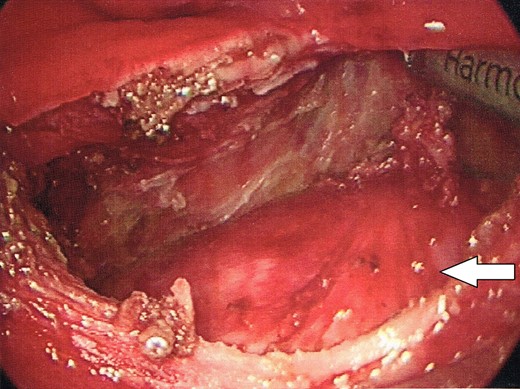

The dome of the cyst is visible at the bottom of the image (indicated by arrow), with a dissection plane visualized above.

The cyst was completely liberated from all attachments using TAMIS, with the exception of the caudal extent. The caudal extent of the cyst was unable to be adequately visualized with the TAMIS platform. Therefore, the transanal port was removed, and the resection of the distal extent of the cyst was completed transanally. The mass was then extracted transanally (Fig. 6).